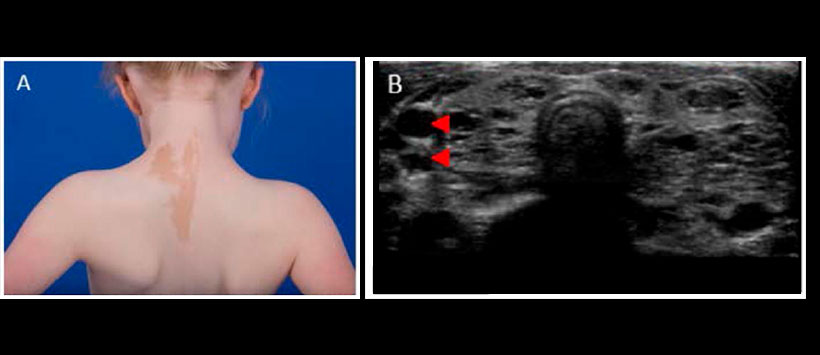

Figura 4: (A) Características de las máculas “café con leche” observadas en el síndrome de McCune-Albright. Los limites se conocen comúnmente como la «costa de Maine» y la lesión normalmente respeta la línea media, siguiendo las líneas de la migración celular (líneas de Blaschko). (B) Ecografía de la tiroides (vista transversal) que muestra lesiones hipoecoicas multiloculares (puntas de flecha), comunes en el síndrome de McCune-Albright